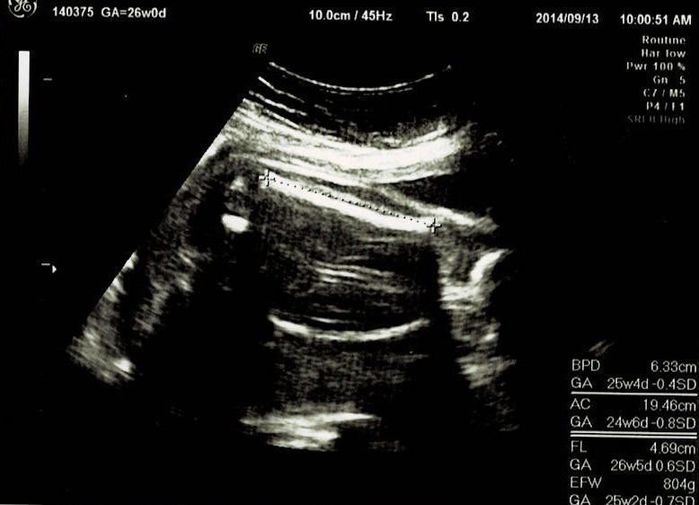

この日は、BPD(頭の左右幅)、AC(おなかの周りの長さ)、FL(太ももの骨の長さ)を測って、赤ちゃんの育ちぐあいを見てくれました。このエコーは足の骨を測っているところです。足の指らしき骨も見えます。先生がスムーズに赤ちゃんの頭やおなか、足を探すのが面白く、測っている最中のエコーもずっと眺めていました。

妊娠19週目エコー写真